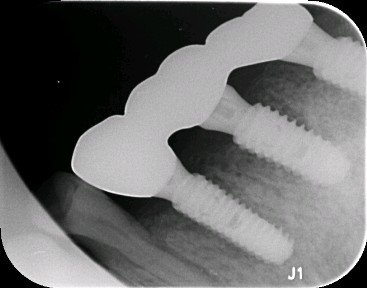

患者男,五十岁,右上后牙缺失一年。治疗计划拔出后种植修复。综合考虑患者自愿选择欧美hiossen种植体。最终15植入hiossen种植体4.5*11.5mm;16、17植入hiossen种植体5.0*10mm。二期三期如期进行。余近日戴牙。